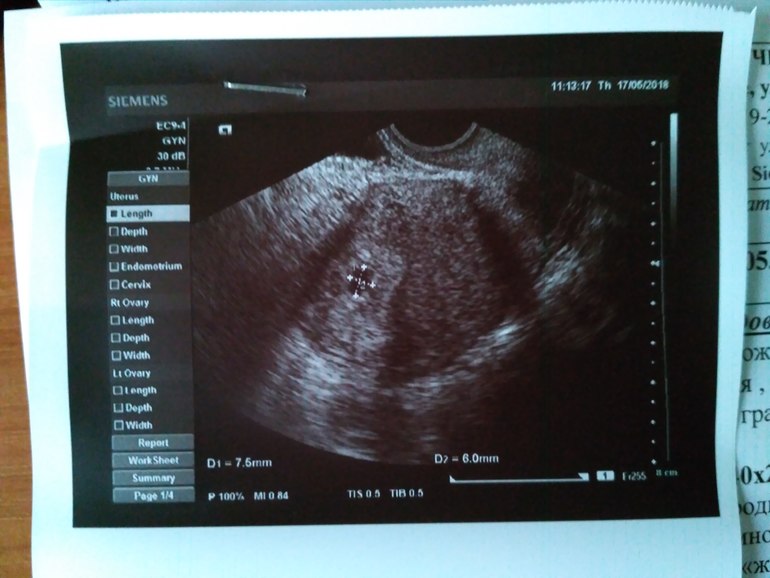

Добрый день, подскажите пожалуйста, срок беременности у меня 5-6 недель. Была на осмотре у гинеколога и на УЗИ. По УЗИ срок подтвердили, тонуса нет. Сразу говорю что у меня нет никаких выделений и ничего не болит. Пью Фолио. По УЗИ увидели рубец от предыдущего КС и спайки. Плодное яйцо 7,5×6 мм. Жёлтое тело 14 мм. На всякий случай сдала анализы на прогестерон и ТТГ. По итогу прогестерон 5,68 нг/мл. Нормы лаборатории 9,3 - 33,4 нг/мл. Гинеколог сказала принимать Утрожестан 200 на ночь в течении недели, далее сдать прогестерон и посмотрим в динамике, увеличивать или так и оставлять. Но я переживаю что маленькая дозировка назначена. Не поздно ли будет что-то корректировать через неделю? Уточняла ещё раз у гинеколога по поводу дозировки. Сказала достаточно одной на ночь. Вставляла уже 3 ночи. Спасибо за ответ